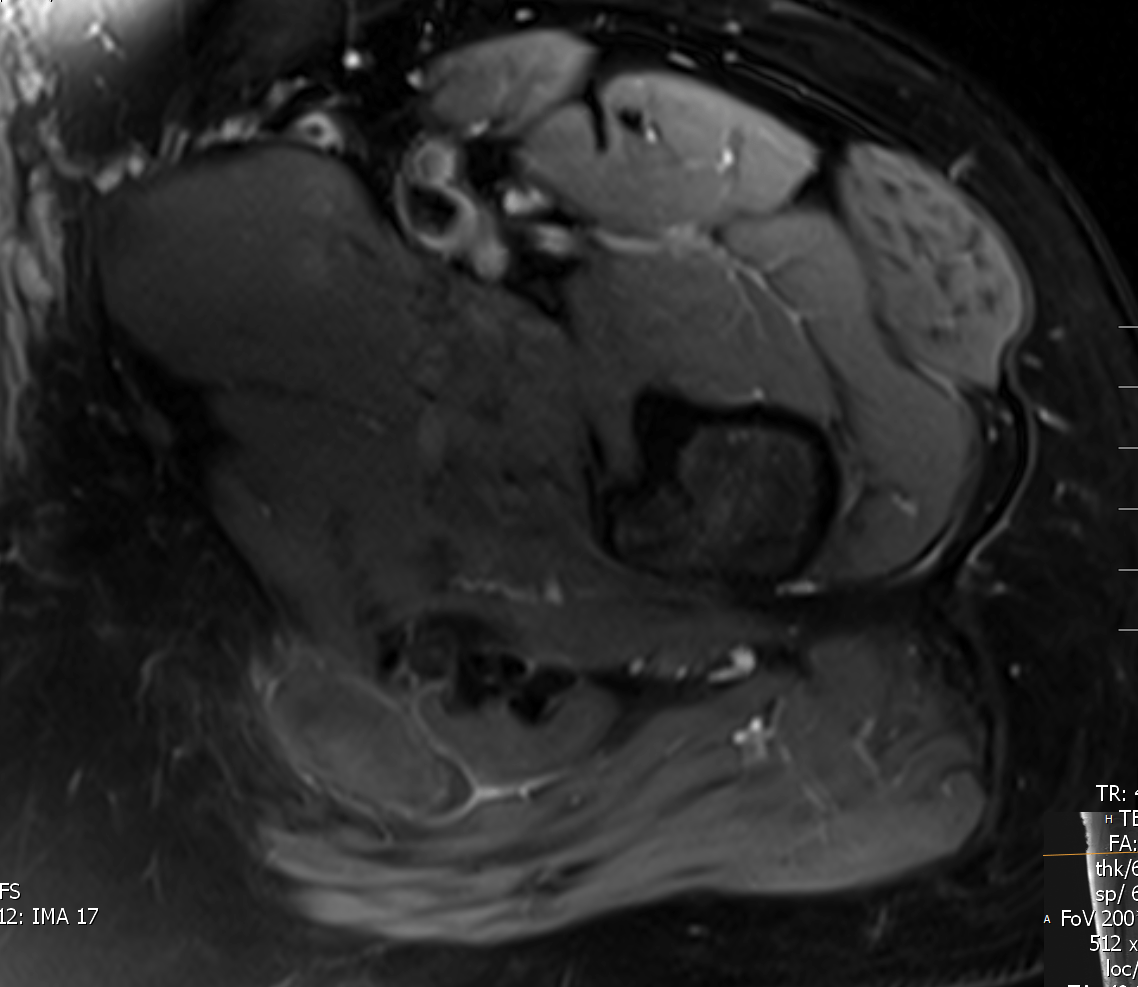

AxPDFS.PNG